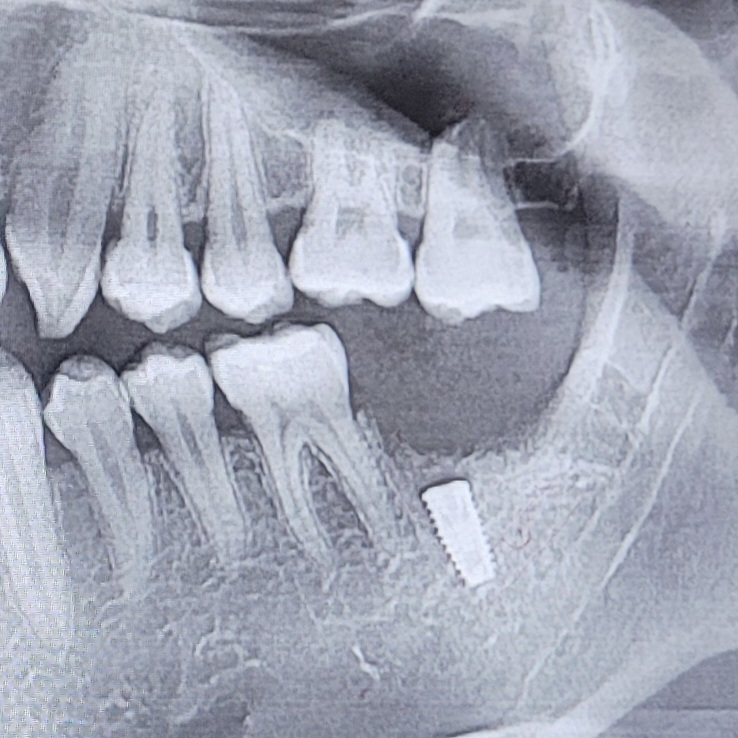

제가 3주전에 어금니를 발치하고 픽스쳐 식립했는데요 사진은 바로 옆 어금니뒷 면 입니다. 두 번째 사진은 발치 전 엑스레이 사진입니다. 마지막은 식립 이후 사진입니다.

• 1번 째 사진